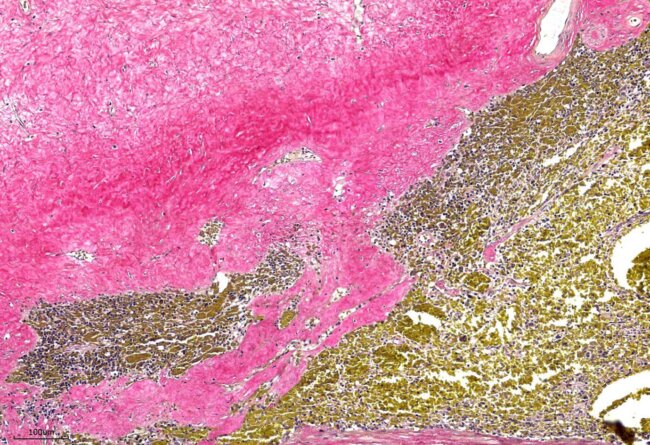

犬口腔T細胞淋巴瘤 (T cell lymphoma)

Picro-Sirius red 天狼星紅染色

Modified Movat’s Pentachrome 染色法